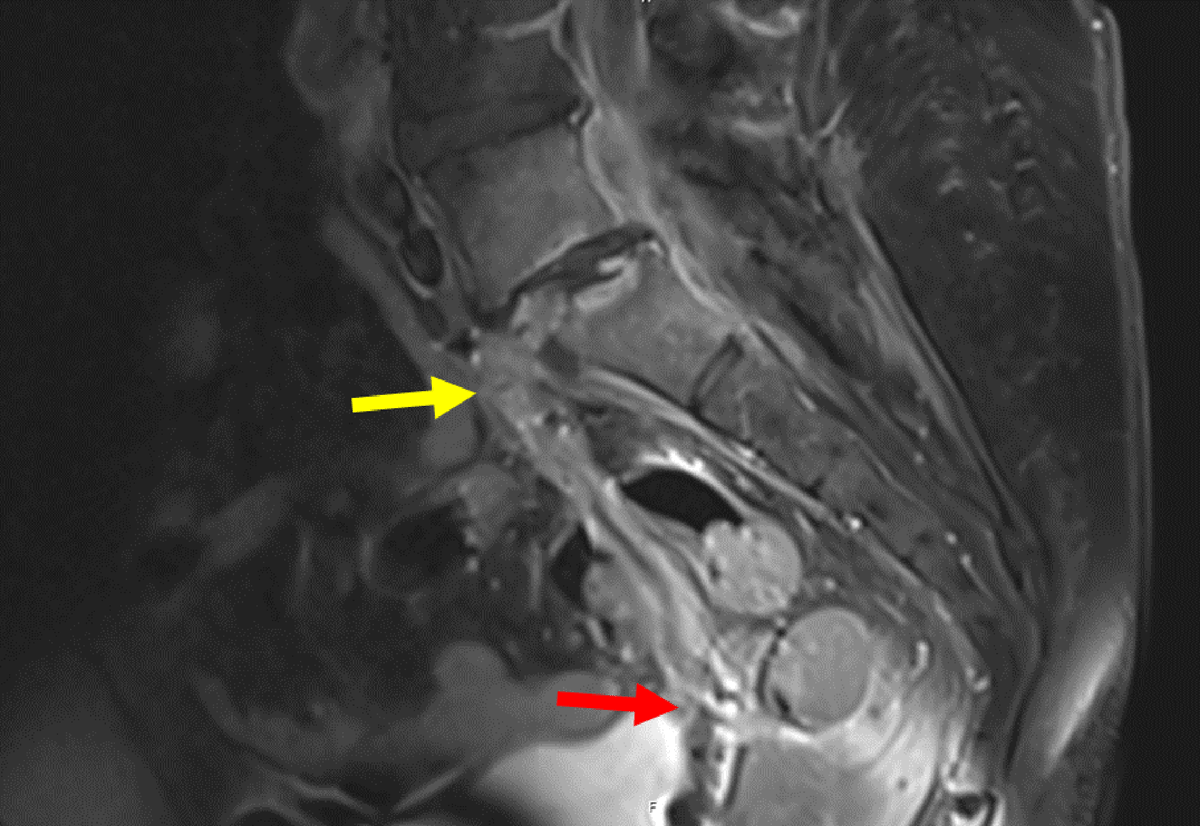

Figure 7

Sagittal contrast MRI in T1 fat saturation weighing: Full path of fistula from L5-S1 (yellow arrow) to the vagina. The fistula (red arrow) presents with a hyperintense wall surrounding a hypointense lumen.